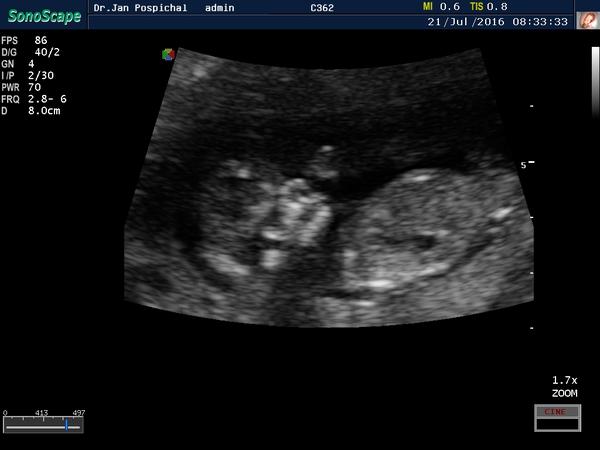

@estrellita bohužel se nechtěl ukázat 😒 tohleto je fotka ze 13tt

@matylda123 kavove zrno tam neni. Bych ti to zakrouzkovala,ale z mobilu to nejde. Muj tata takhle na utz poznal diky mocove trubici nasi treti dcerku v 16 tt,primo v primem prenosu mi ukazal mocovou trubici a jak zrovnw cura a ta trubice byla rovne a koncila spolu s telem. Tady jde sikmo nahoru a jeste vystupuje z tela. Aspon jsem to vyfotila bliz. Tak jsem zvedava 🙂 pri dalsim utz nspis. A fotku zespoda nemas?

@matylda123 ruka vede niz,sleduj kost od raminka,ta je hezky videt.